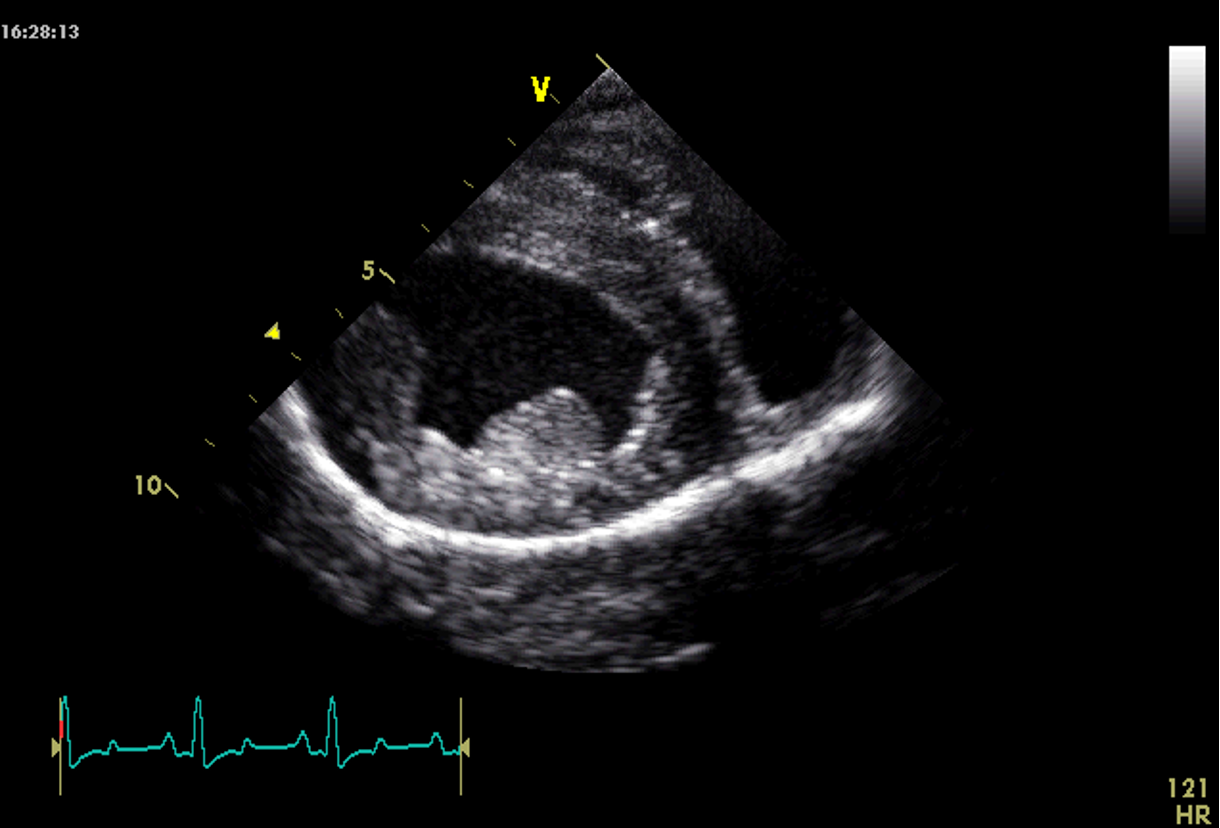

Which view is this?

Right parasternal long axis 4 chamber

Q

A